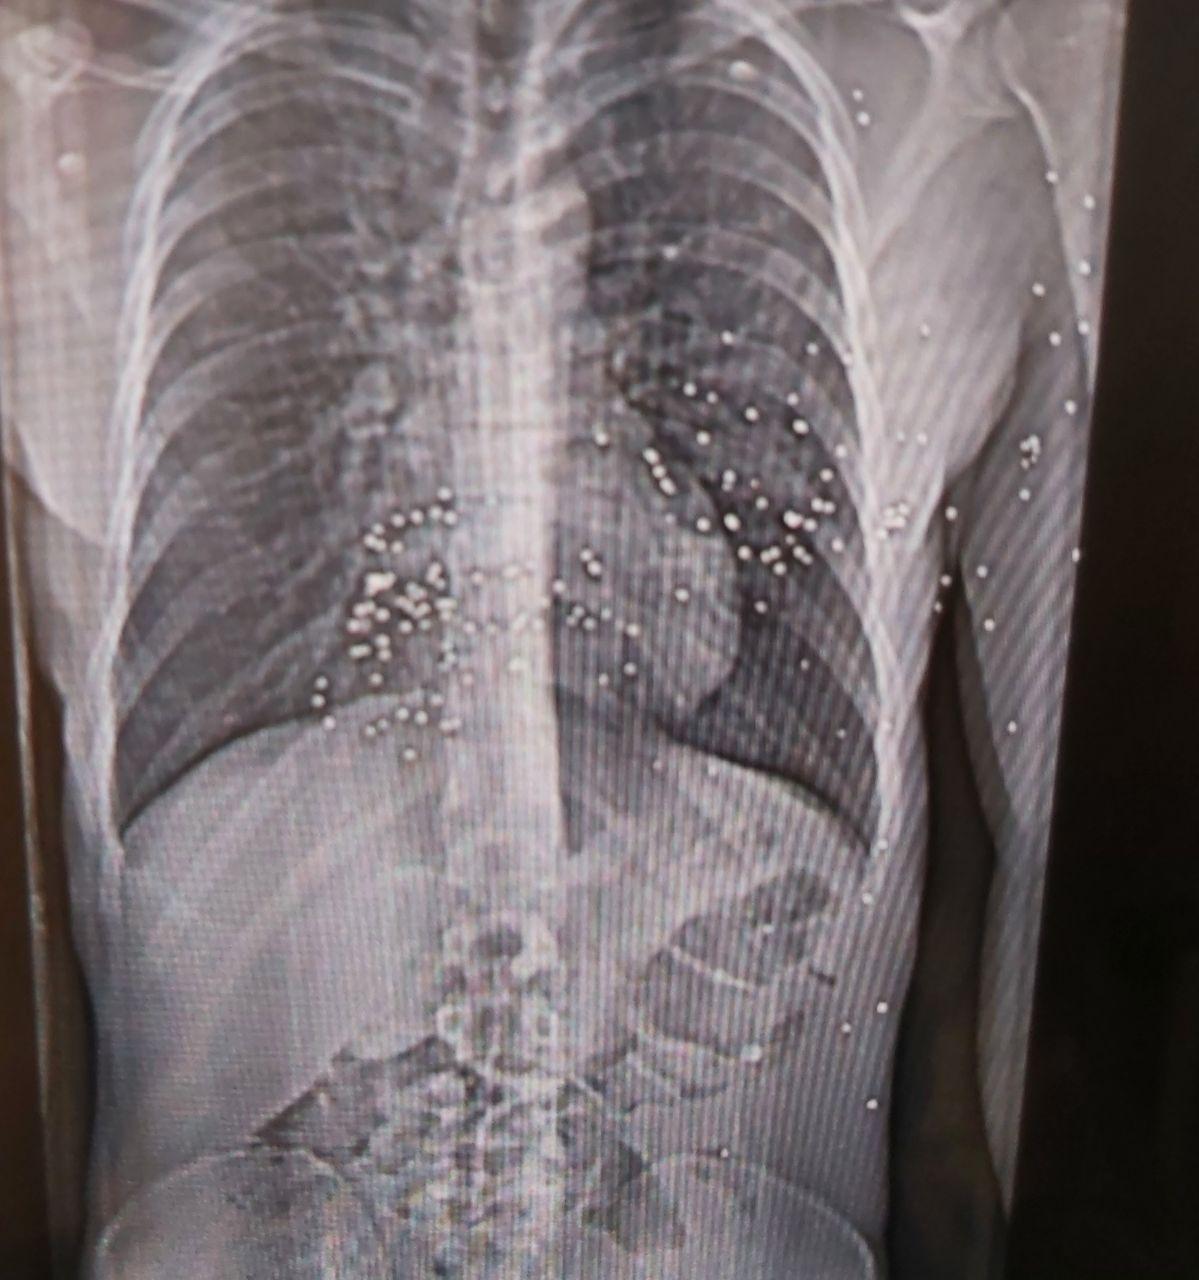

نیویورکر نوشت ‏اعضای کادر درمان در هفته‌های اخیر خود به مستندسازی شواهد حملات حکومت به مردم ایران پرداخته‌اند و برخی مدارک از جمله تصاویر سی‌تی‌اسکن مجروحان را در اختیار این مجله قرار داده‌اند.

نرگس این وضعیت را «جهنمی» توصیف کرد: نوجوانی ۱۴ ساله با پاهایی نحیف که با ساچمه‌های فلزی هدف قرار گرفته بود؛ مردی با حفره‌ای به اندازه توپ تنیس در ساق پا که او در بخیه‌ زدن آن کمک کرد.